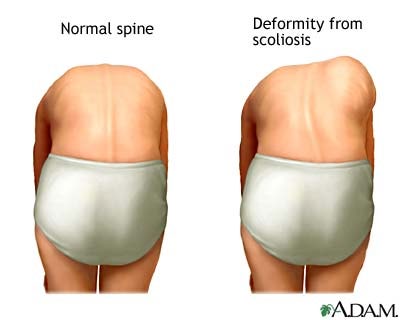

La scoliosi idiopatica è una deviazione laterale della colonna. La scoliosi è legata al fatto che ruotano le vertebre e deformano la gabbia toracica , con la comparsa del gibbo. Se è una scoliosi lombare, l’effetto sarà che diventano asimmetrici, ossia diversi i fianchi.

Necessaria una diagnosi precoce. Bisogna individuare riconoscere una Scoliosi «vera» tempestivamente. Non confonderla con un Atteggiamentodi scoliosi. La Scoliosi «vera» ha una rotazione delle vertebre e quindi ha il gibbo e un andamento evolutivo e richiede un trattamento specifico, invece l’ Atteggiamentonon progredisce e si risolve una volta risolta la sua causa.

E’ una diagnosi clinica. Esame da dietro della colonna con il ragazzo/a in piedi e con la colonna flessa in avanti (test di Adam) Ricerca del Gibbo a livello toracico e/o della Asimmetria dei fianchi e della Prominenza Lombare.

Sempre con lo stesso test. L’atteggiamento è una deviazione laterale della colonna vertebrale senzarotazione vertebrale e senzadeformità dei corpi vertebrali. ASSENZA DEL GIBBO/PROMINENZA LOMBARE Nell’atteggiamento scoliotico facendo flettere in avanti il paziente (Adam’s Test), la colonna vertebrale si riallinea e NONcompare il gibbo costale, che invece è tipico di scoliosi strutturata. Anche in posizione supina le vertebre si riallineano eladeviazione scompare completamente. Gli atteggiamenti scoliotici si trattano risolvendo le cause che li hanno provocati, ad esempio compensando l’accorciamento dell’arto inferiore con un rialzo. Non sono necessari trattamenti ortopedici specifici o ginnastica correttiva. L’atteggiamentopuò essere per una Dismetria degli arti inferiori, ossia una diversa lunghezza con il bacino che si inclina dalla parte dell’arto più corto o di Scoliosi antalgica, ossia legata ad una contrattura con deviazione della colonna per effetto del dolore, per esempio un’ernia del disco.